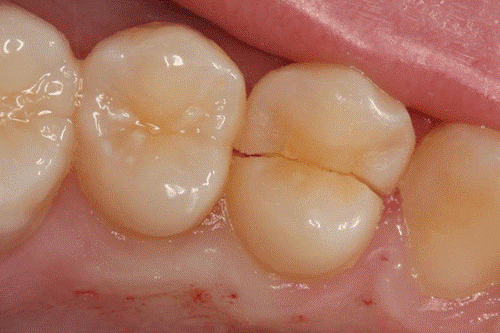

- شکستگی کاسپ: هنگامی که قسمت جونده ی دندان بشکند یا ترک بردارد اما این ترک به بالاتر از قسمت جونده پیشرفت نکند را شکستگی کاسپ گویند.

در اکثر مواقع دندانپزشک کل دندان را می ساید و پس از آن روکش مناسبی بر روی دندان ها قرار می دهد. روکش ها باعث محافظت و زیبایی بیشتر دندان های شما می شود. اگر دندان در قسمت جونده دچار شکستگی شده باشد نیز دندانپزشک قسمت شکسته شده را با مواد مخصوص پر می کند و روکشی برای محافظت از دندان بر روی آن قرار می دهد، ما اگر ترک دندان تا نزدیک لثه پیش رفته باشد می توان با کمی سختی و درد آن را درمان کرد.